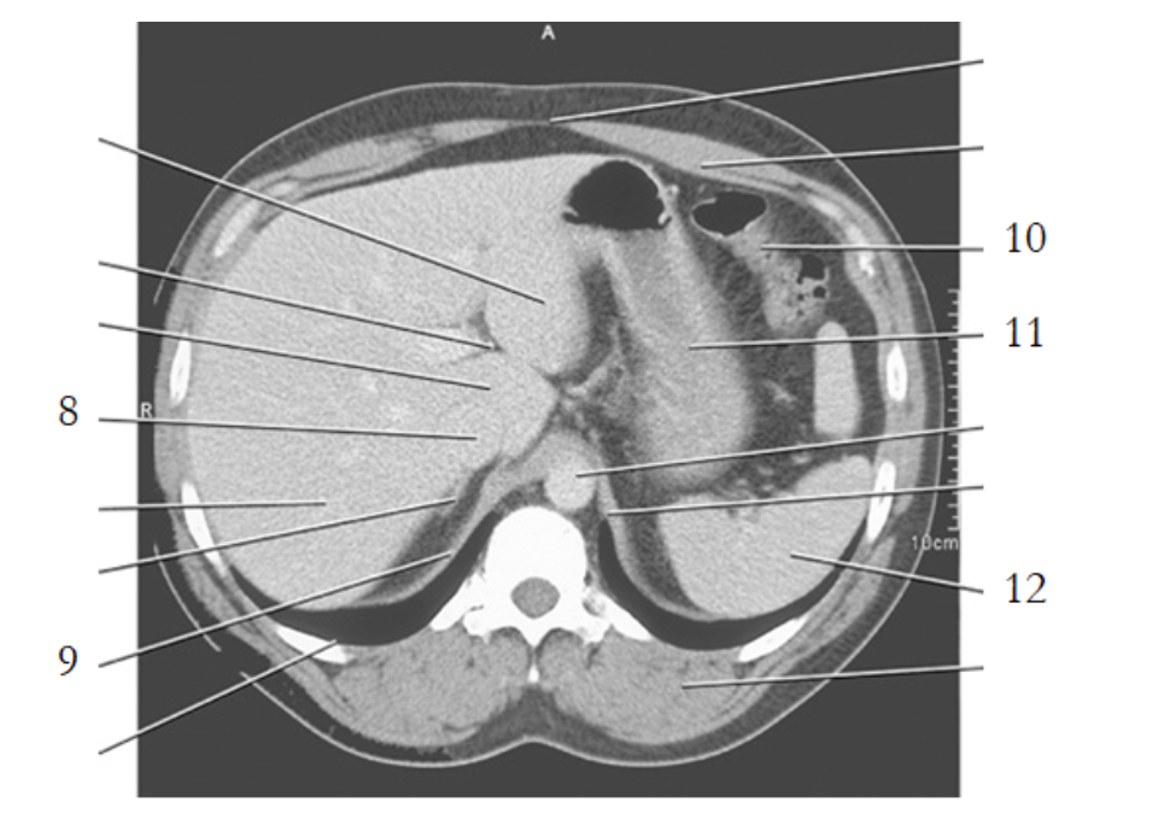

11

celiac axis

12

splenic artery

15

portal vein

spleen

13

pancreas tail

16

kidney

14

gallbladder

21

large bowel

25